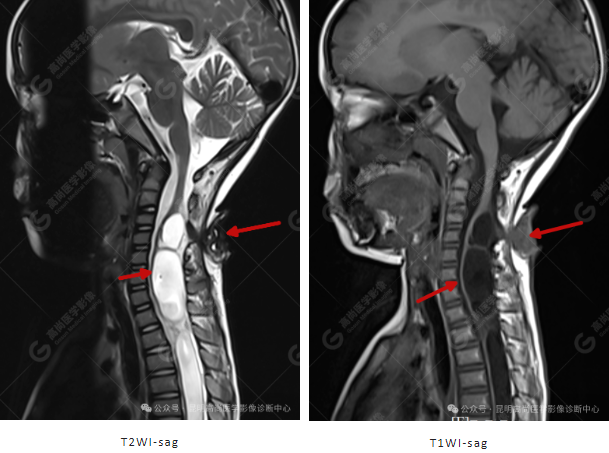

患者女,5 岁,出生时发现颈部包块,大小 3 cm×3 cm,5 年来无变化,拟行手术治疗,要求增强核磁协诊,否认体内金属物,无过敏史。

影像表现

颈 3-5 层面颈后部软组织不规则片状异常信号影,脊膜膨出可能;颈 3、4 棘突局部显示不清;颈胸髓内(约颈 3-胸 9 椎体水平)异常信号影,考虑囊肿并局部颈髓空洞可能,肿瘤或其他待排;请结合临床及相关检查。